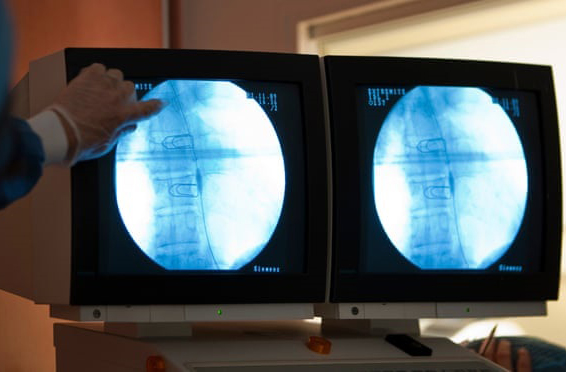

Phẫu thuật thực quản được thực hiện bằng cách sử dụng máy tăng cường ảnh. Ảnh: Getty Images